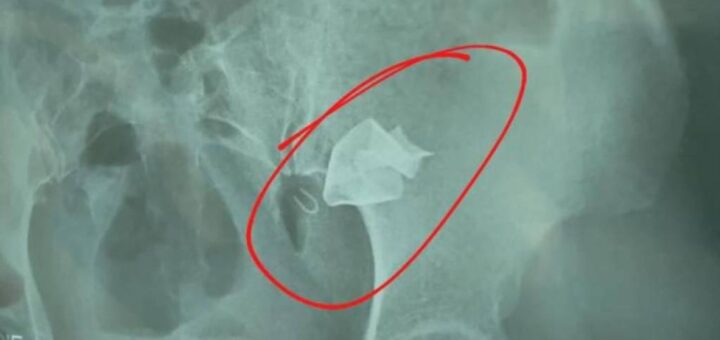

Uncategorized junio 5, 2023 MUJER A LA QUE LE DEJARON UNA GASA EN EL ESTÓMAGO SERÁ OPERADA POR CUARTA VEZ Silvia Escalante es la mujer a la que le dejaron una gasa en el estómago para el nacimiento de su bebé... 0 0CompartirTwittear0 Compartir